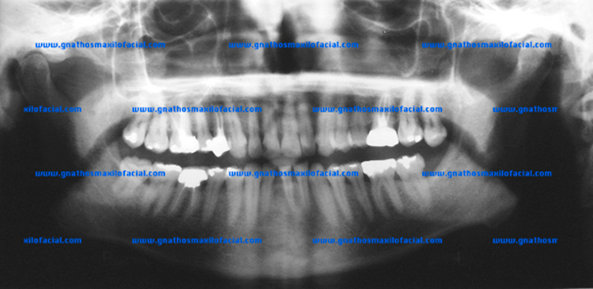

| Malposiciones dentales severas en un paciente con erupción activa de los 3os molares | |